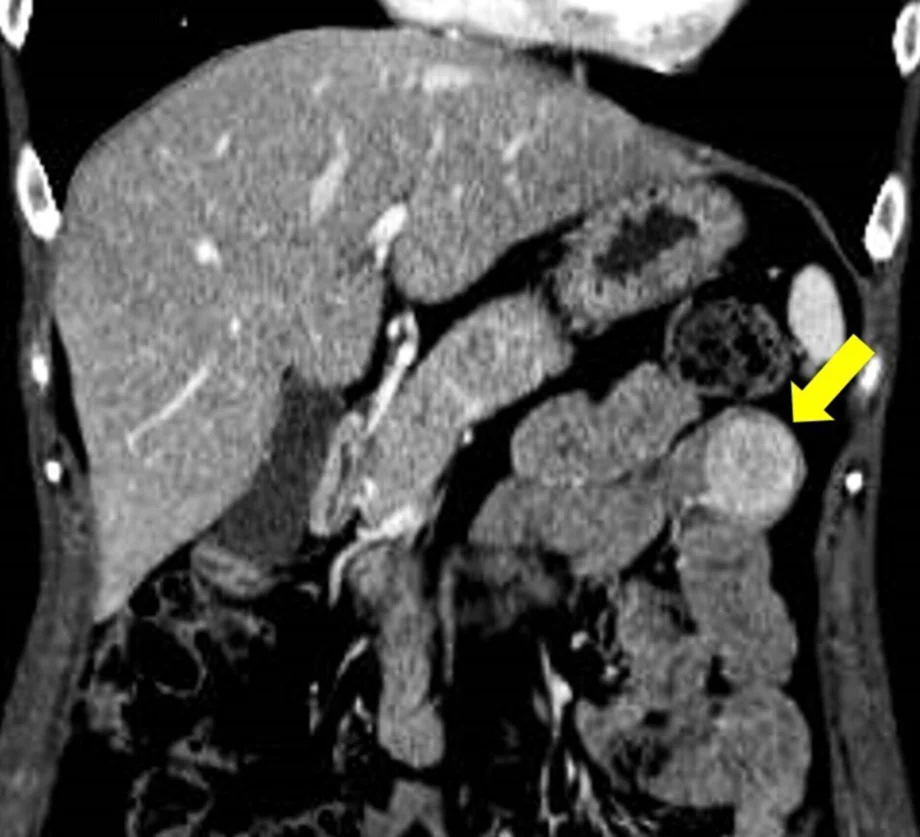

Transgastric endoscopic ultrasound-guided fine needle biopsy for diagnosing gastrointestinal stromal tumor of the jejunum

Yuichi Takano, Fumitaka Niiya, Masatsugu Nagahama

DEN image